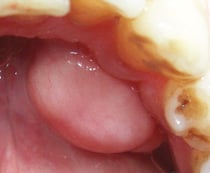

③ 骨隆起

長年の強い咬み合せの衝撃から歯を支えている骨が反応して、コブのように盛り上がった状態です。この骨隆起自体には何の害も無いため心配ありません。

しかし歯がなくなってしまい入れ歯が必要になったときにはとても邪魔な存在になり、この骨隆起が原因で入れ歯の痛みに悩まされるケースも多くあります。